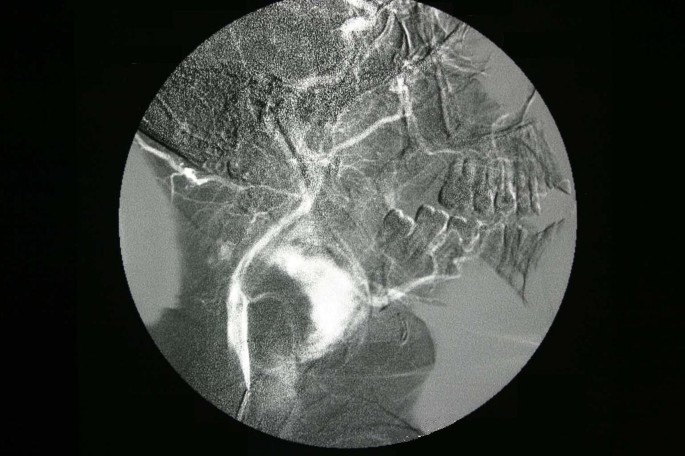

Scintigraphic examination of the thyroid gland revealed homogenous distribution of the activity in the gland but no activity was noticed in the mass adjacent to the gland. Angiography and doppler usg findings suggested that the tumor had rich vascularity and the main blood supply was from the superior thyroid artery (Figure 3, 4). The fine needle aspiration of the mass revealed the cellular aspirates with no colloid, and aspirates which included some microfollicular aggregates. However, no papillary folds, psammoma bodies, or nuclear grooves were detected (Figure 5). It was reported as "solid cellular nodule, microfollicular lesion".